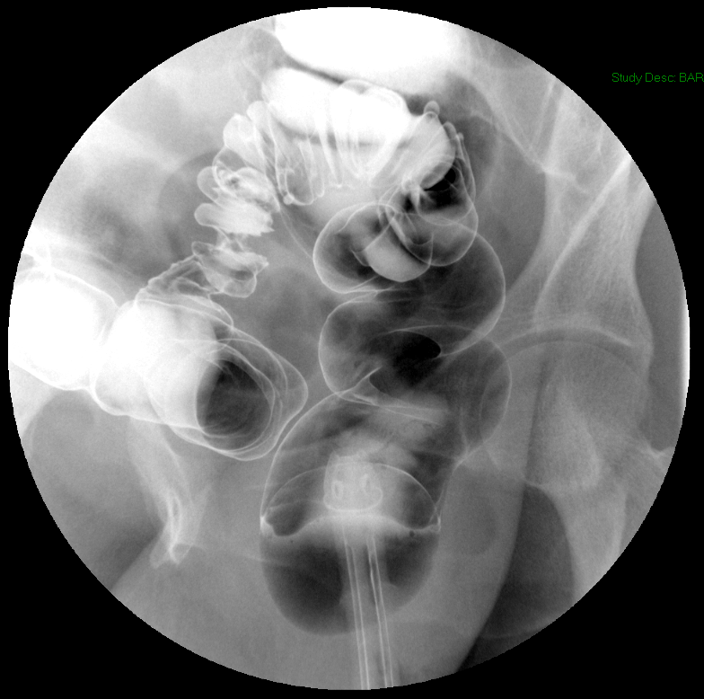

Double Contrast Barium Enema

Return to Table of Contents

- To note:

- Double contrast barium enema (DCBE) examinations have mostly been replaced by colonoscopy, either conventional or virtual, however DCBE examinations are still ordered occasionally.

- Method:

- The technologist will obtain a scout image

(key image 1).

- Review the scout image, looking for any contraindications to performing the procedure (pneumoperitoneum, pneumatosis, etc.).

- Once you have determined it is ok to proceed with the examination, have the patient lie in the Sims position.

- Lubricate the enema tip then place it gently into the patient's rectum.

- Move the fluoroscope over the patient.

- When ready, the technologist will infuse some of the barium into the rectum.

- Using real time fluoro, evaluate to see if the patient's rectum is distended with barium. If distended, use the white insufflator to inflate the balloon on the enema tip while watching with real time fluoro. The technologist will clamp the balloon for you.

- The technologist will continue to infuse the barium. Once all the barium has been infused, the technologist will clamp the enema tubing.

- Begin SLOWLY insufflating air into the colon using the blue insufflator. Air should be insufflated no quicker than one puff per second.

- Insufflating the air too quickly can cause abdominal cramping for the patient.

- In some instances, insufflating air too quickly can also cause the air to move ahead of the barium within the colon creating an air-lock and the barium will not progress throughout the entire colon.

- Raise the head of the table to 45 degrees.

- The technologist will unclamp the enema tubing and allow the excess barium and air to drain out of the rectosigmoid colon.

- Once drainage has stopped, the technologist will clamp the tubing.

- Turn the table horizontal again.

- Slowly insufflate enough air to distend the rectosigmoid colon.

- Obtain spot images of the recto-sigmoid colon with the patient in the left posterior oblique and right posterior oblique positions

(key image 3)

(key image 4).

- Have the patient roll onto their left side and raise the head of the table to 75 degrees.

- The technologist will unclamp the tubing and allow excess barium to drain.

- Obtain images of the hepatic and splenic flexure with the patient in the left anterior oblique and right anterior oblique positions

(key image 5)

(key image 6).

- The technologist will clamp the enema tubing. Turn the table back to horizontal and have the patient roll onto their left side.

- Place the table in Trendelenburg 10 degrees.

- Obtain a spot image of the cecum with the patient in supine or right posterior oblique position

(key image 7).

- One last time turn the table to upright 45 degrees.

- The technologist will unclamp the enema tubing and allow excess barium to drain. When done, the technologist will re-clamp the tubing.

- Turn the table into horizontal position.

- Slowly insufflate enough air to distend the colon.

- The technologist will obtain post study overhead radiographs:

- PA to include the entire colon

(key image 8)

- PA angle (35 degrees caudal), patient positioned in slight RAO (~15 degrees), to include the rectosigmoid colon

(key image 9)

- RPO (~45 degrees), to include the splenic flexure

(key image 10)

- LPO (~45 degrees), to include the hepatic flexure

(key image 11)

- AP angle (35 degrees cephalad), patient positioned in slight LPO (~15 degrees), to include the rectosigmoid colon

(key image 12)

- Right decubitus, to include the entire colon

(key image 13)

- Left decubitus, to include the entire colon

(key image 14).